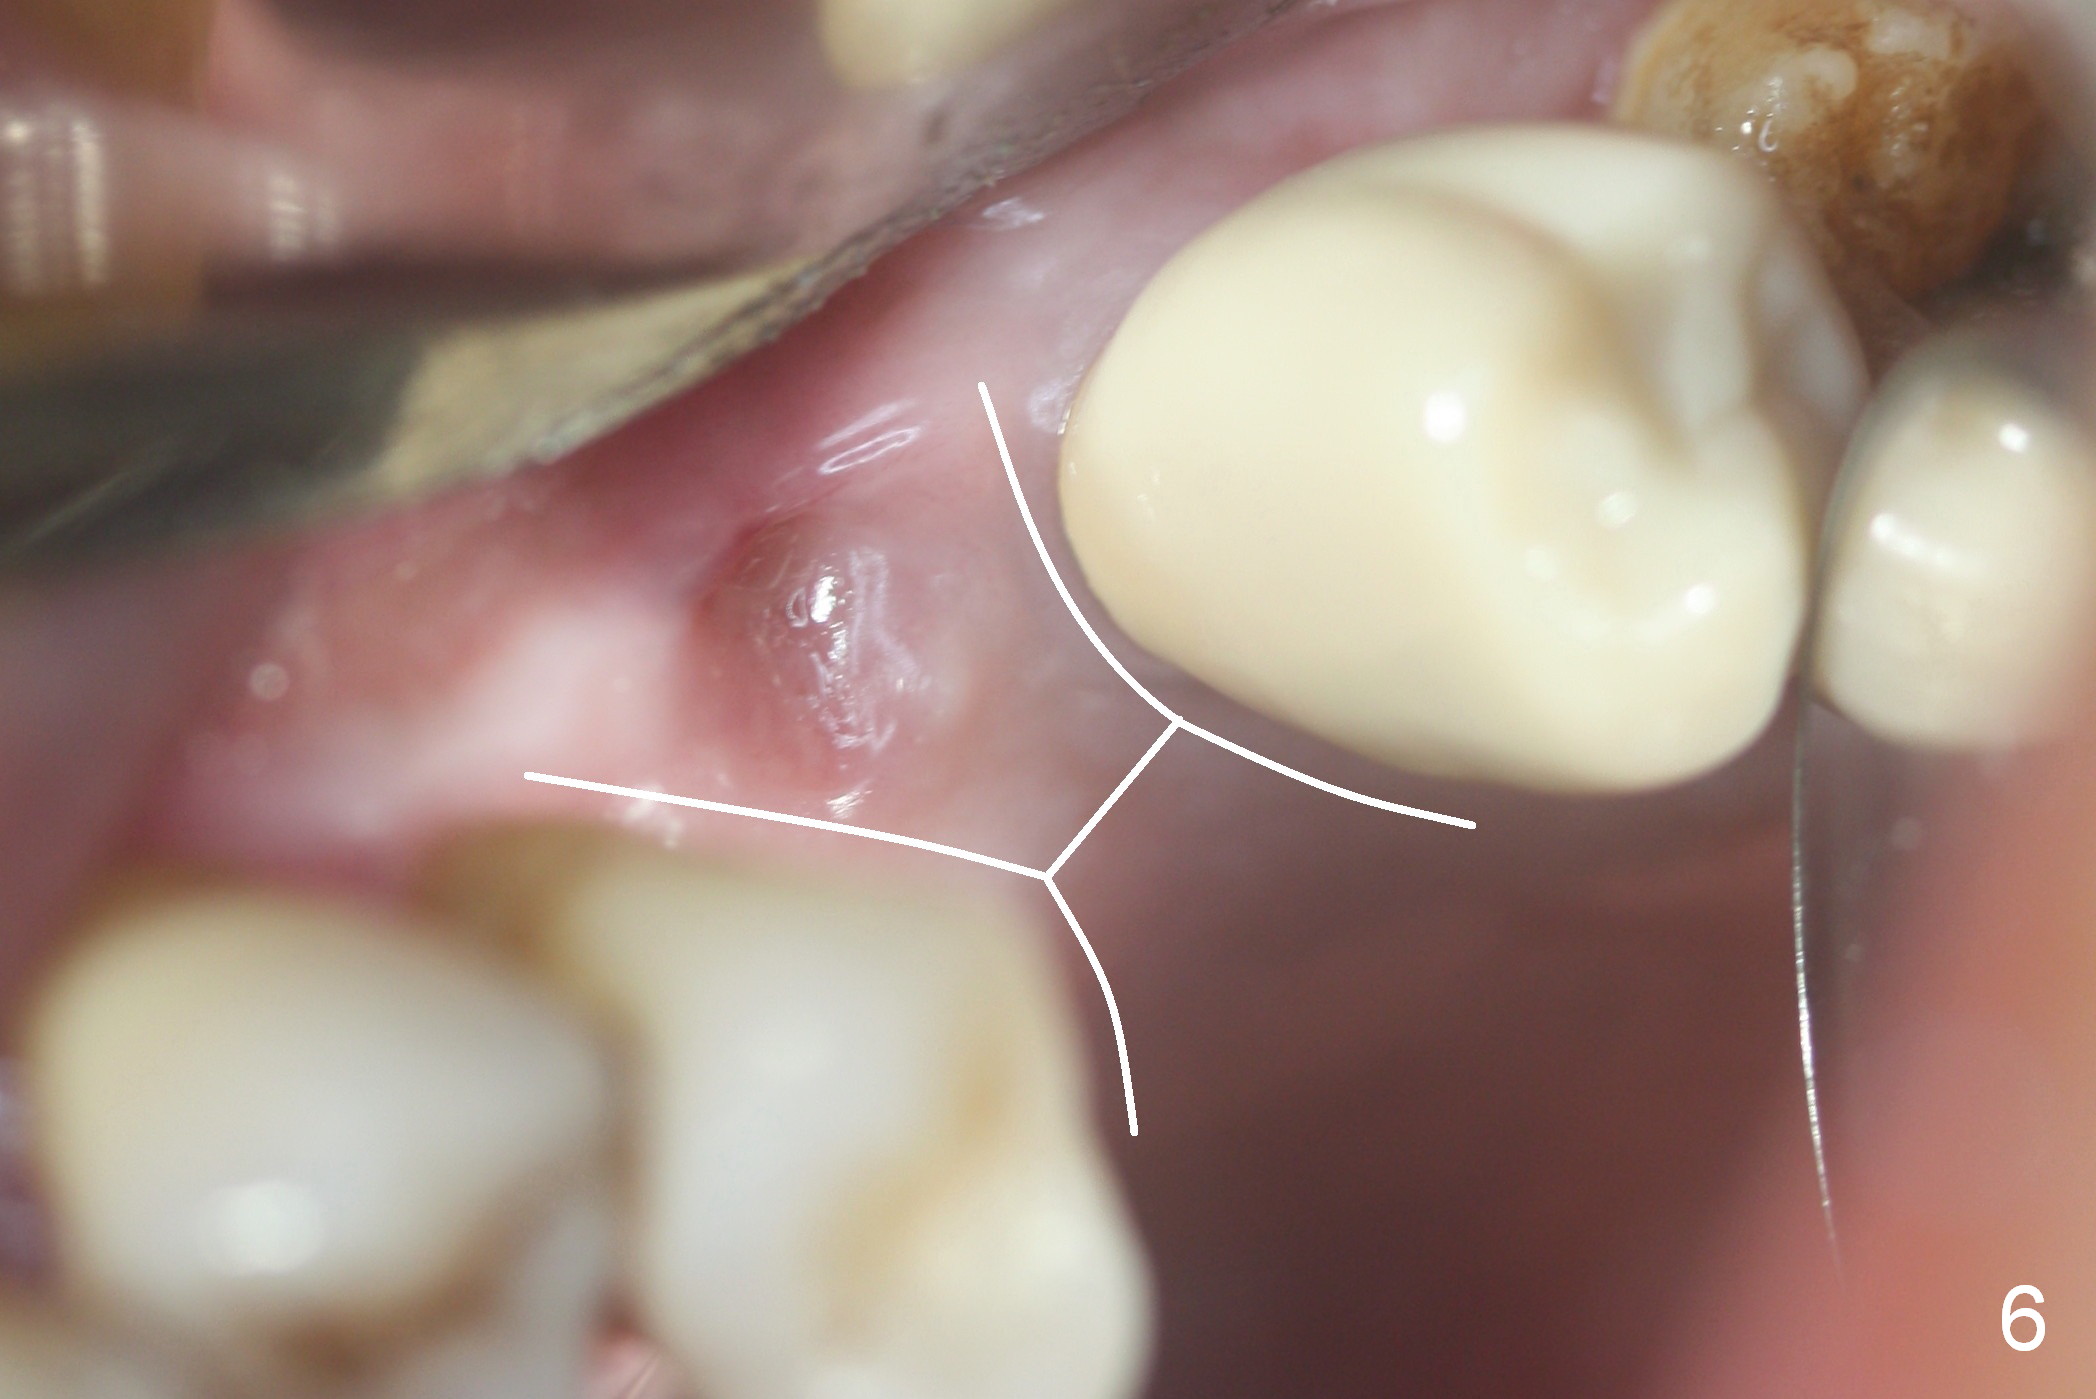

The implant site is healing a few days after loss (Fig.4 *) with a bony defect (Fig.5 ^). It appears that the implant at #14 was placed buccally. An incision is made palatally because of the presence of more keratinized gingiva (Fig.6). The buccal bone height is limited. The soft tissue in the bony defect is lifted into the sinus before bone graft (Fig.7 *).